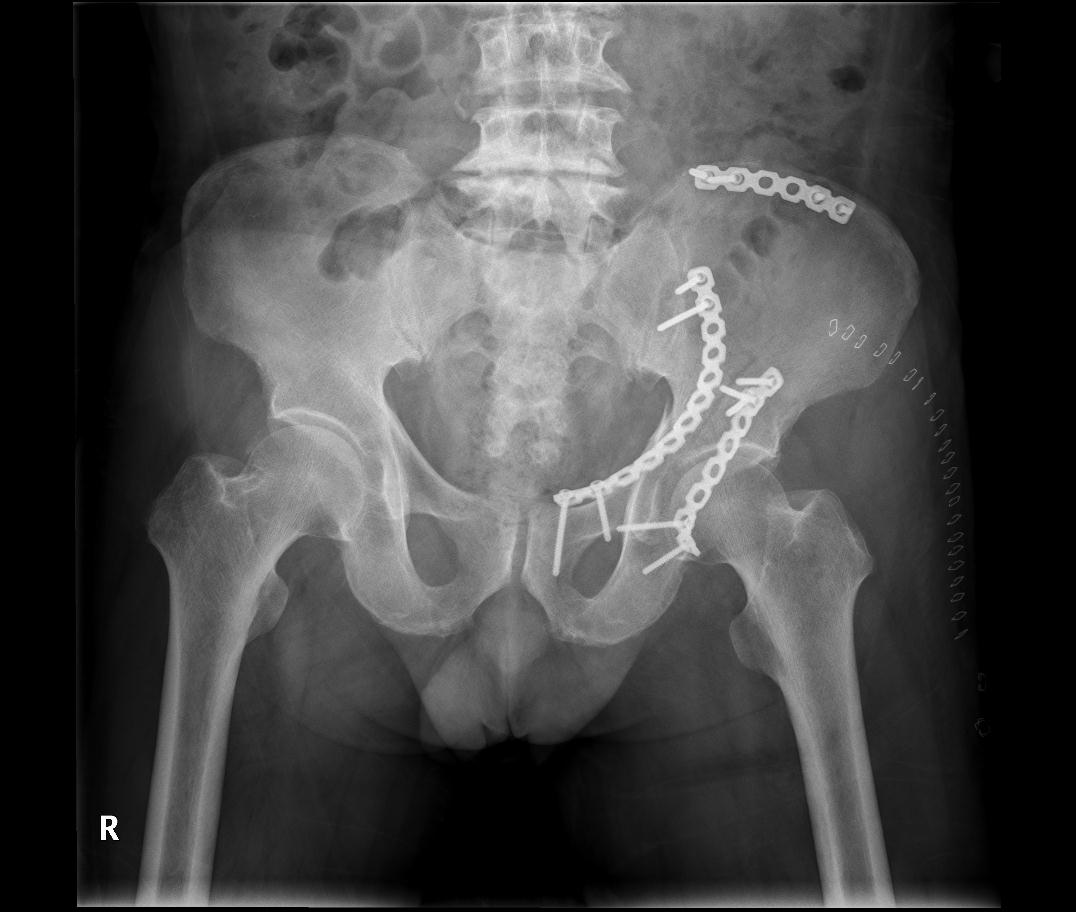

영상 진단: X-ray, CT 스캔, MRI 등을 통해 골절의 정확한 위치와 심각성을 확인합니다.

수술적 치료: 심각한 골반 골절의 경우, 수술을 통해 뼈 조각을 복원하고 고정할 수 있습니다.

치료: 대부분의 비구 골절은 수술적 치료가 필요합니다.